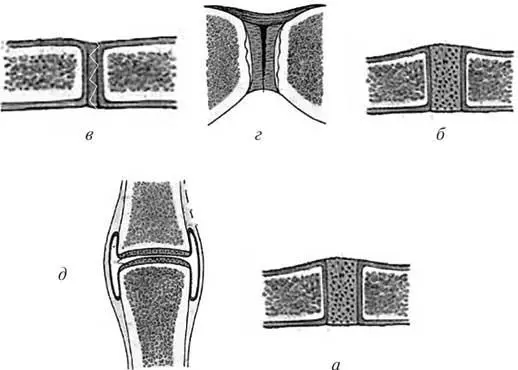

Структура и анатомия синдесмоза: научные иллюстрации